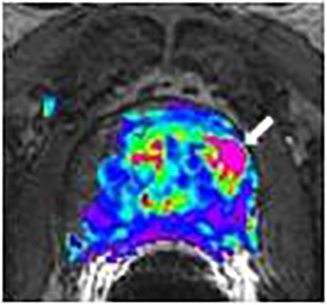

Diffusion weighted imaging (DWI): DWI is a technique involving the exchange of water molecules (diffusion) between prostate tissue compartments Figure 1c. Diffusion rates vary between normal and pathologic tissue. With DWI, the MRI machine is set to detect small restrictions in the free movement of water within the prostate gland and provide information about cellular crowding, seen in areas of increased cell turnover.

Dynamic contrast enhancement (DCE): is an MR technique that gives information on tumor angiogenesis (Figures 2a-2c).

Figure 2 is biopsy proven prostate adenocarcinoma in a 62-year-old man with a Gleason grade of 6 (3+3). This example shows how functional imaging can help identify the tumor.

prostate_mri_6

prostate_mri_8

prostate_mri_7

prostate_mri_9

Figure 4: Following the diagnostic MRI he underwent a MRI Guided prostate biopsy where only 2 cores were obtained through the left sided suspicious region in the prostate gland.